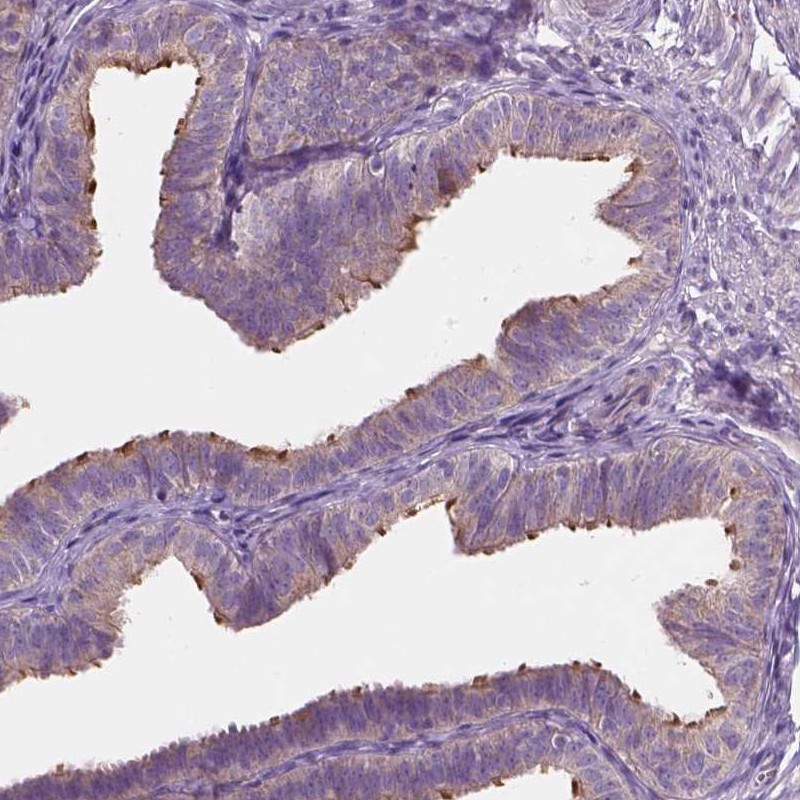

Immunohistochemical staining of human fallopian tube shows positivity in cilia.